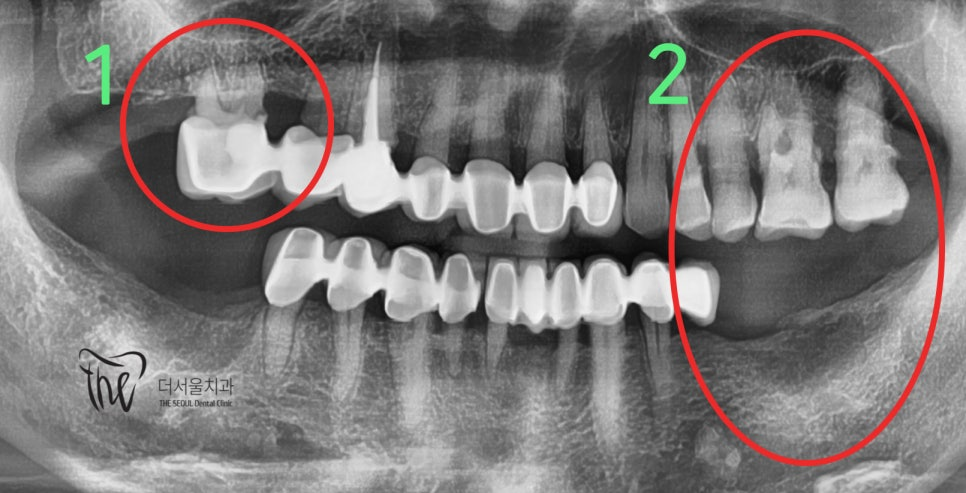

앞니가 빠졌어요! 어쩌죠? 이럴 때는 조금 침착하게 생각을 해야 됩니다. 먼저 가까운 치과에 하루 빨리 내원을 하셔서 현 상황을 정확하게

어금니쪽과 다르게 앞니 쪽에는 치아 뿌리를 감싸고 있는 치조골의 폭경이 좁습니다. 즉, 추후 임플란트 를 심으려 했을 때 충분한